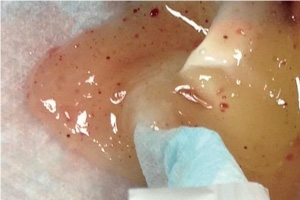

- 液状化したシリコンの様子

- 取り出したシリコンバッグ

「バッグが破れても漏れ出さないはず」のシリコン。ところがTHE CLINICでは、他院のバッグ摘出の際、体内に流れ出しているシリコンがドッとあふれ出してくる例を何例も手掛けています。破損してから時間がたつと、体液が少しずつ混ざっていき、液状化することが原因です。

今回のケースでも、もともと透明だったシリコンに体液が混ざり、変色し始めていました。放置すれば、被膜の外にまでシリコンが漏れ出していた可能性があります。脇の下から破れていたしていたバッグを取り出し、シリコンを入念に洗浄しました。